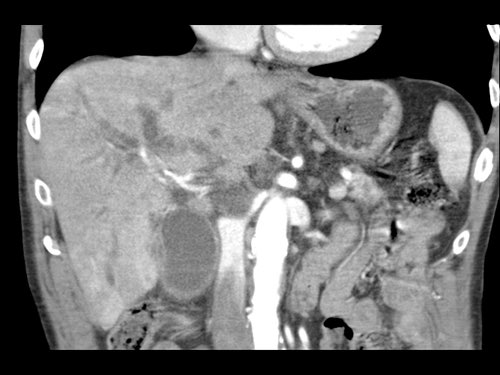

Tái tạo mặt phẳng coronal cho thấy một khối u lớn xuất phát từ cổ tụy với kiểu phát triển xâm lấn (hình A và B).

Có hiện tượng bao quanh động mạch thân tạng 360º (mũi tên trong A).

CT axial MIP tại mức động mạch thân tạng cho thấy hẹp động mạch gan chung bị bao quanh (mũi tên), rất nghi ngờ xâm lấn.